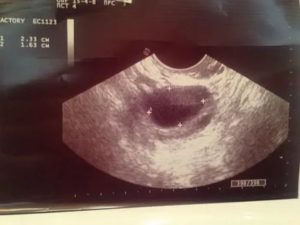

Выглядит на УЗИ желтое тело, как анэхогенное образование. Отсутствие эхогенности обусловлено его содержимым. Внутри находится жидкость, обрамленная ровным контуром без дополнительных камер. Находится желтое тело на поверхности яичника, где ранее располагался доминантный фолликул. Дополнительным показателем функции желтого тела становится толщина эндометрия.

Оценить состояние лютеинового тела до овуляции на УЗИ не получится – его еще не существует. Железу можно наблюдать при ультразвуковом исследовании сразу после освобождения яйцеклетки из яичника. В первые несколько часов тело только начинает образовываться, поэтому не всегда удается ее определить. УЗИ лучше делать на 3-4 день после овуляции.